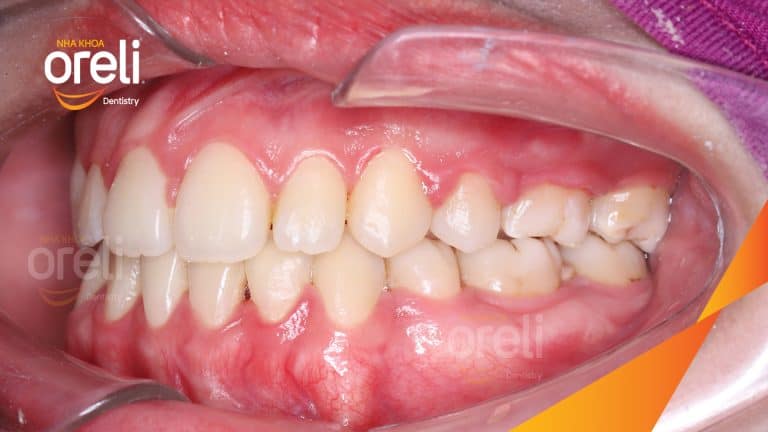

Ca niềng chỉnh chen chúc sai khớp cắn hạng 3 móm nhẹ – Kết quả thực tế ở Oreli Niềng răngChen chúcMóm Xem thêm